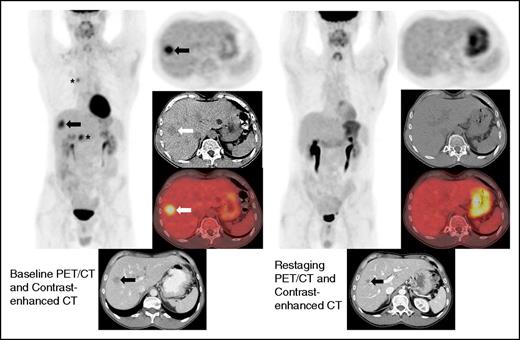

Restaging FDG-PET/CT and contrast-enhanced CT at 19 weeks demonstrates interval resolution of FDG uptake in a liver lesion. Restaging contrast-enhanced CT shows interval decrease in size of the hepatic lesion (arrow). Because the lesion did not disappear, this patient achieved a PR by immune-related response criteria, whereas the absence of FDG uptake on FDG-PET/CT is a CR by the Lugano Classification. There was also a complete metabolic response in the mediastinum and right upper abdomen (asterisks).